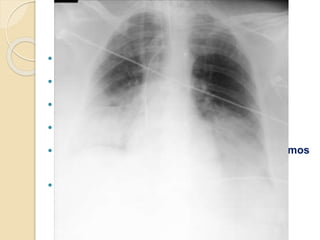

 Evolución PULMONAR:

◦ IOT (17/02/2014)

16/02/201425/02/2014 tras CC01/03/2014 1º bolo CFM10/03/2014 tras

plasmaféresis

19/03/2014 tras 2º bolo

CFM

06/04/2014 tras 3º bolo CFM

EVOLUCIÓN CLÍNICA PACIENTE Evolución PULMONAR: ◦ VMNI ◦ IOT (17/02/2014) ◦ Traqueostomía (19/03/2014) ◦ FBC  confirma hemorragia alveolar 16/02/201425/02/2014 tras CC01/03/2014 1º bolo CFM10/03/2014 tras plasmaféresis 19/03/2014 tras 2º bolo CFM 06/04/2014 tras 3º bolo CFM